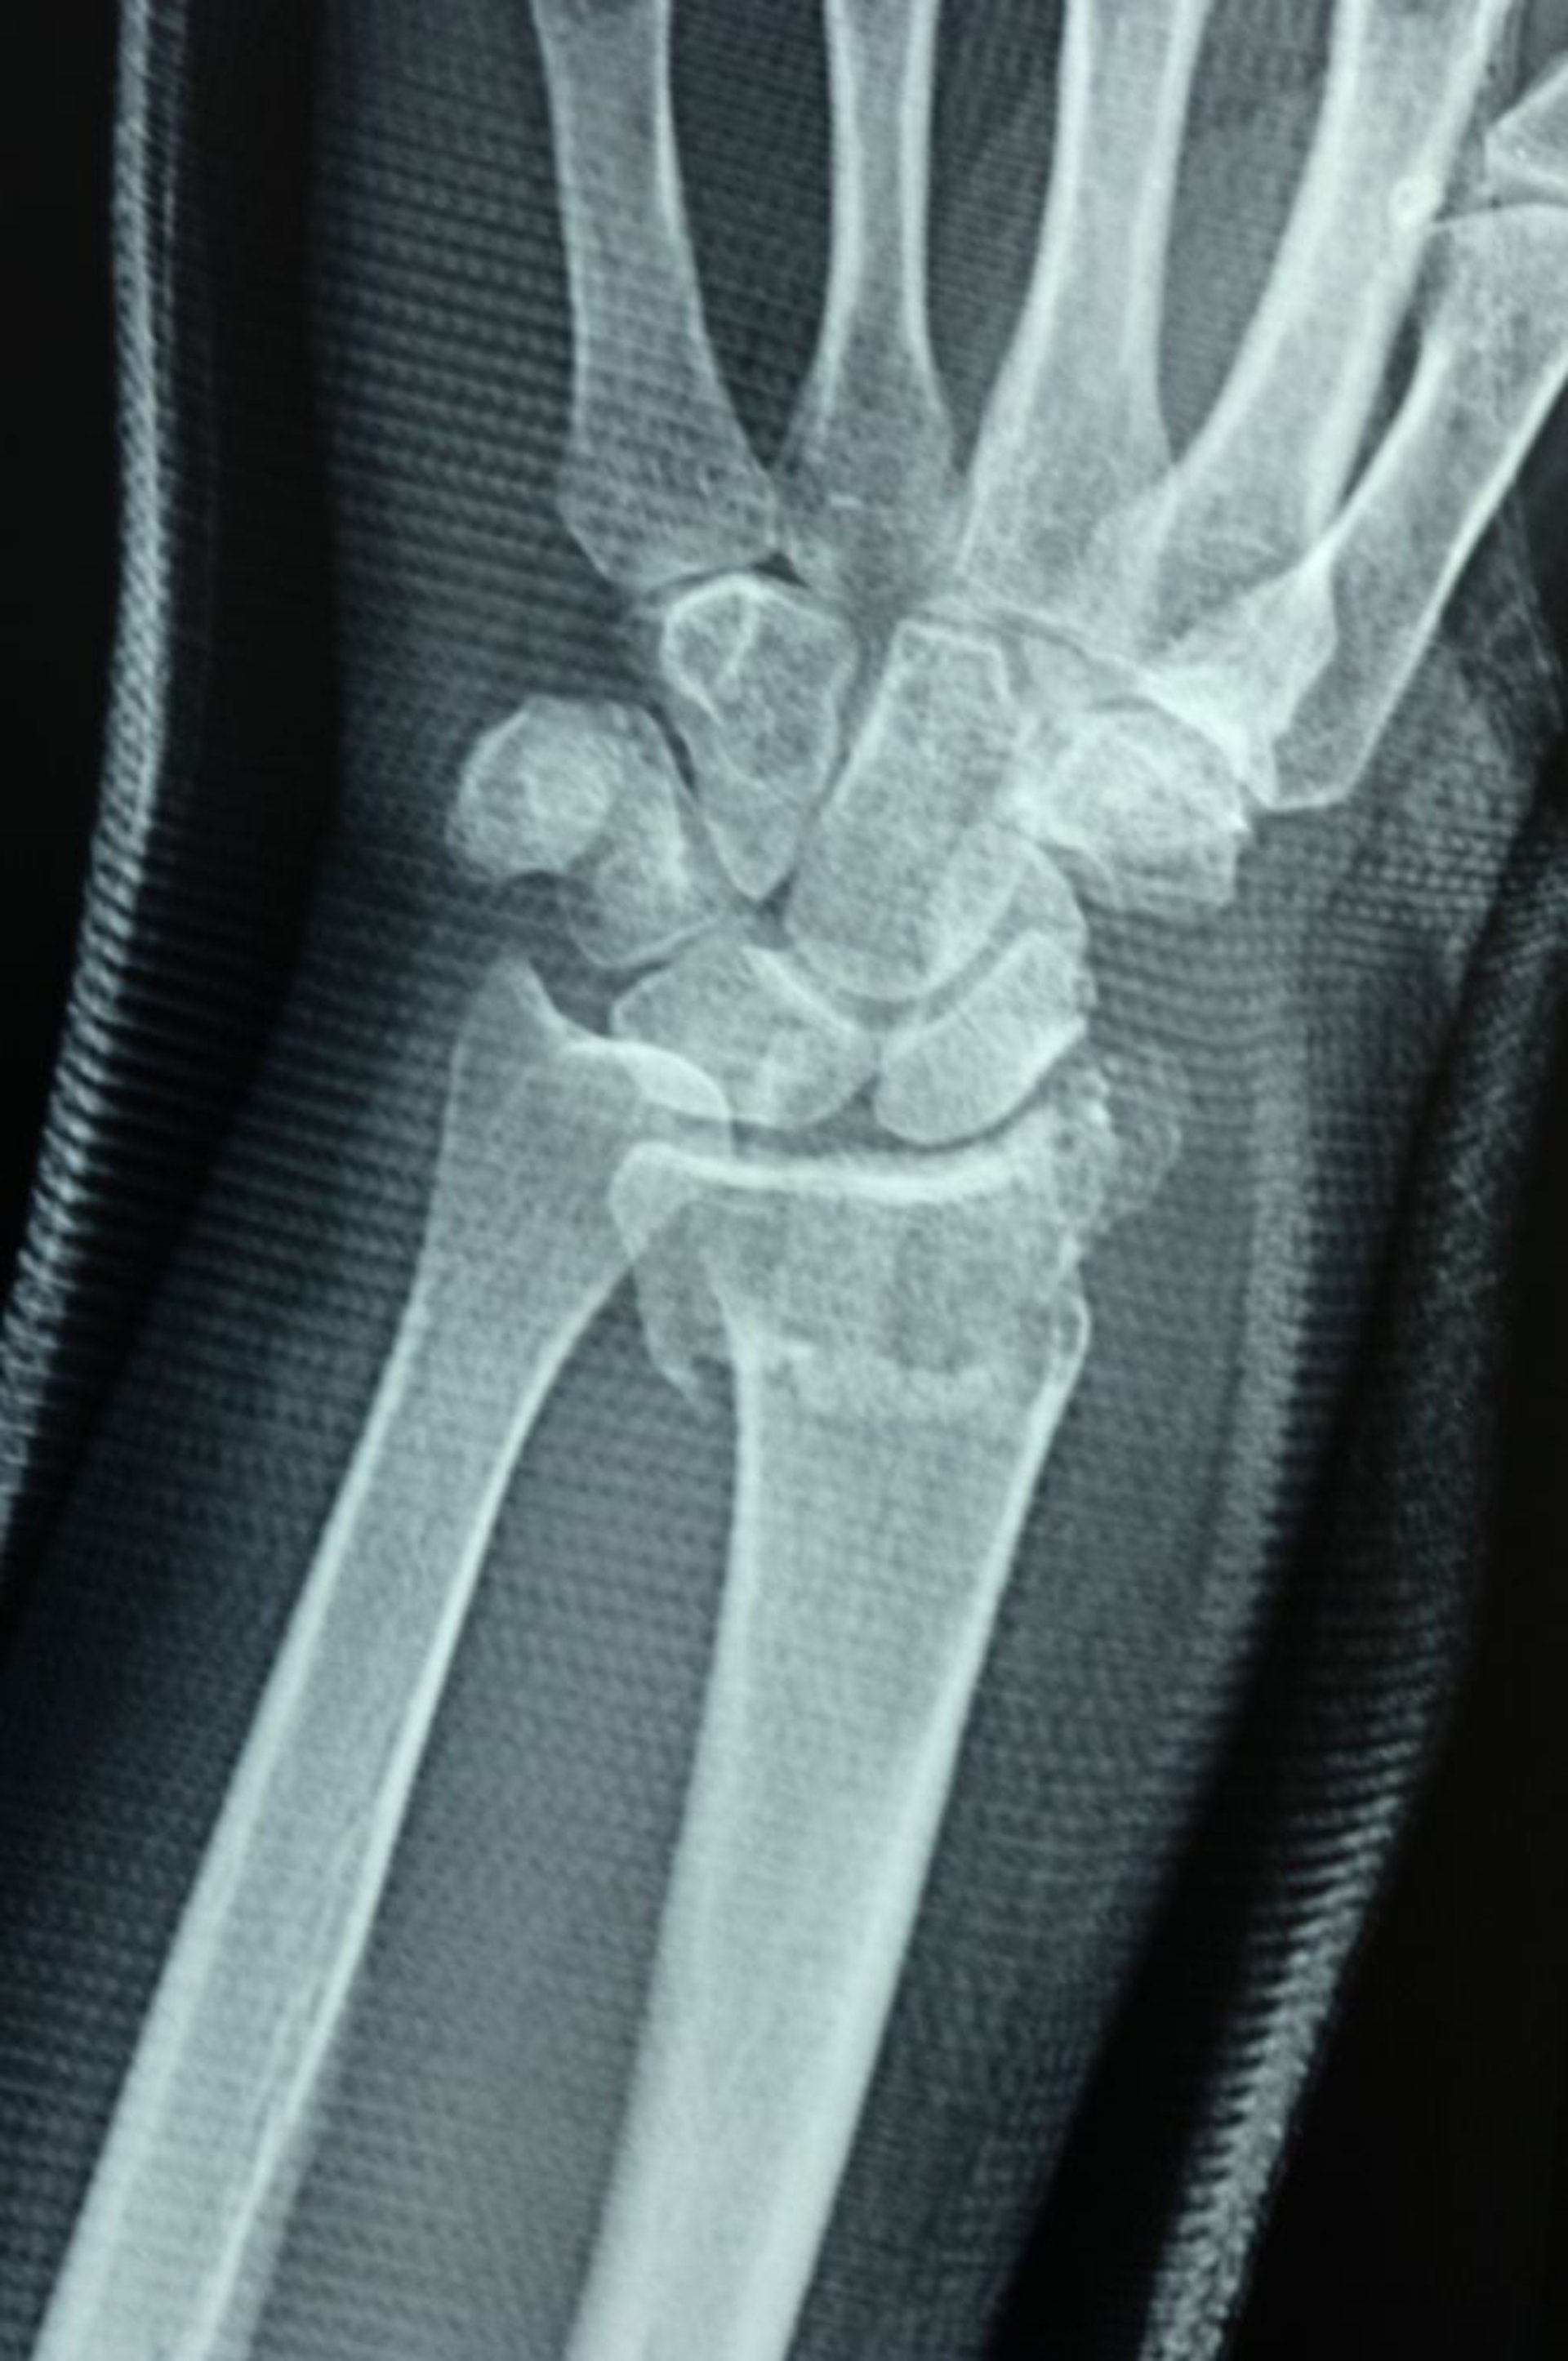

Fractura distal del radio

La articulación radiocubital se separa, lo que se demuestra por la falta de alineación de las superficies articulares del radio distal y el cúbito distal, lo que provoca un escalón.

DR P. MARAZZI/SCIENCE PHOTO LIBRARY